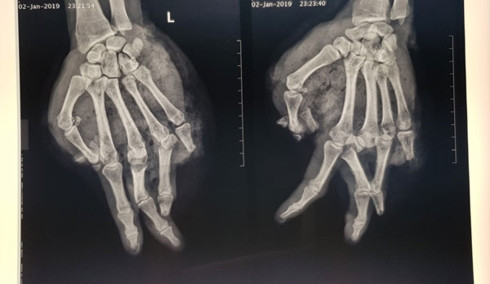

Hình ảnh phim chụp X-quang cho thấy bàn tay của bị bệnh nhân bị chấn thương (Ảnh: Bệnh viện cung cấp)

Bác sĩ Vũ Hữu Trung, Khoa Chấn thương Chi trên và Vi phẫu thuật, Bệnh viện Trung ương Quân đội 108 cho biết, bệnh nhân có vết thương phức tạp, dập phần mềm và lóc da bàn tay trái. Người này còn bị dập nát ngón tay số I, V và đốt 2,3 ngón tay số IV; gãy hở nền xương đốt 1, ngón tay III, IV.